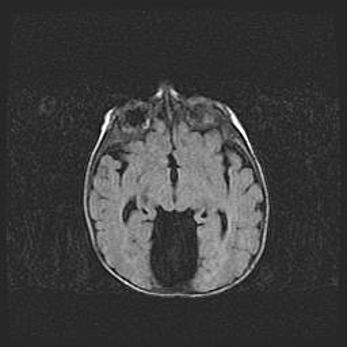

Церебральная ишемия II.

Возраст: 5 дней

Вес: 3400 г

Пол: женский

Окружность головы: 35 см

Срок гестации: 39 недель

Церебральная ишемия – это заболевание, характеризующееся недостаточностью (гипоксией) либо полным прекращением (аноксией) снабжения мозга кислородом по причине закупорки одного или нескольких сосудов. Это приводит к  что метаболическим расстройствам различной степени тяжести в тканях головного мозга, развитию коагуляционных некрозов и гибели нейронов.